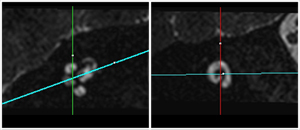

MRI imaging of the inner ear